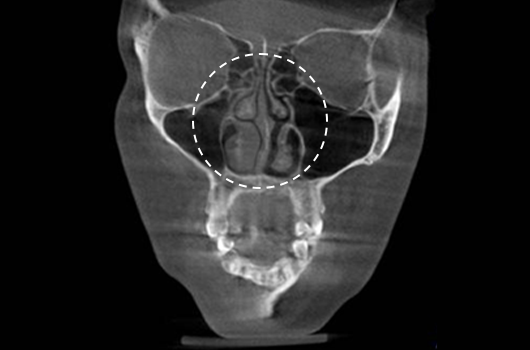

Importance of 3D-CT Scan in Rhinoplasty

During every consultation for rhinoplasty, Braun Plastic Surgery Clinic uses 3D-CT scan to analyze the following issues in three dimensions: A precise surgical plan can be established, and potential side effects reduced by thoroughly understanding the size, shape, and asymmetry of the invisible portions of the nose and the nearby anatomical structures prior to surgery.

1. Analysis of septal cartilage in various sizes and shapes

Analysis of septal cartilage in various sizes and shapes

2. Diagnosis of deviated nose and septal deviation

Diagnosis of deviated nose and septal deviation